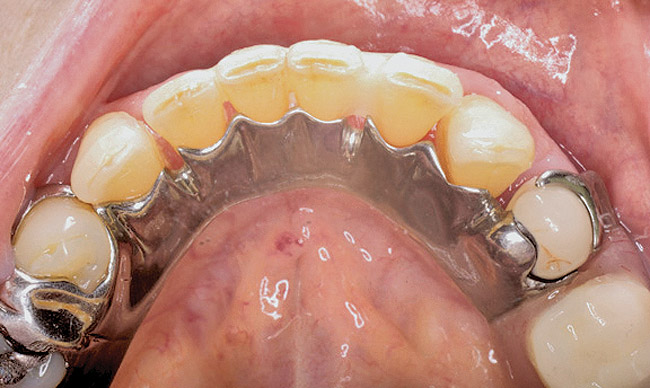

Figure 13  Occlusal view of composite splint.

Figure 13

Figure 10 shows a periodontal patient who was taking oral bisphosphonates for osteoporosis. The patient had full-mouth scaling and root planing, then was given 2 months to heal and instructed to rinse with chlorhexidine twice daily. After no signs of BRONJ were observed, the patient had full-mouth osseous surgery on her few remaining teeth in the mandible. The surgery was performed all at once and not according to the sextant approach because the patient was on a heart and lung transplant list and was moved up the list while healing from the scaling and root planing. The patient also had extensive bone loss in her anterior mandible (Figure 11). To avoid performing extractions, a simple composite splint was placed between the partial dentures (Figure 12 and Figure 13). The splint reduced the mobility of the teeth and made them less likely to be knocked out during any surgical intubation procedure.